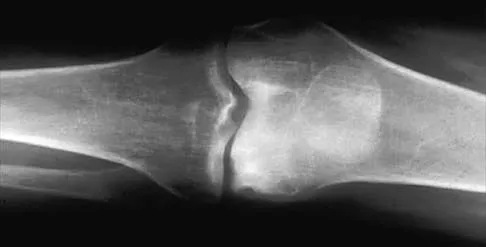

A 66-year-old woman who previously underwent hemiarthroplasty 2 years ago for a fracture continues to have severe pain and loss of motion despite undergoing physical therapy. A radiograph is shown in Figure 2. What is the most likely reason that this patient has failed to improve her motion?

Explanation